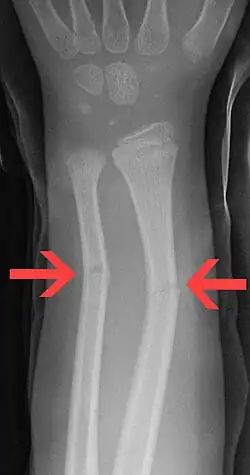

Greenstick fractures on X-ray.

A greenstick fracture is a partial bone break that typically occurs in children due to their more flexible and resilient bone composition. This fracture pattern is characterized by a break on one side of the bone while the other side remains intact and bends, similar to breaking a young, green tree branch. Greenstick fractures most commonly affect the long bones of the forearm (radius and ulna) but can also occur in other long bones throughout the body. Treatment generally involves immobilization with a cast to allow proper bone healing, though in some cases, it may be necessary to realign the bone before casting.

On the side of the fracture that underwent tension, imaging may show bone cortex disruption. On the side that underwent compression, cortex may bulge outward, similar to a torus fracture.[1]

Greenstick fractures are usually identified with ease on X-ray of the affected limb, showing a long bone fracture that does not cut all the way through.[2]